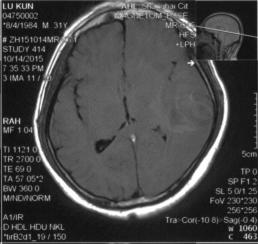

脑MRI:左侧横窦条索状高信号,左颞叶脑出血,见图3&6、7、8

图6

图7

图8